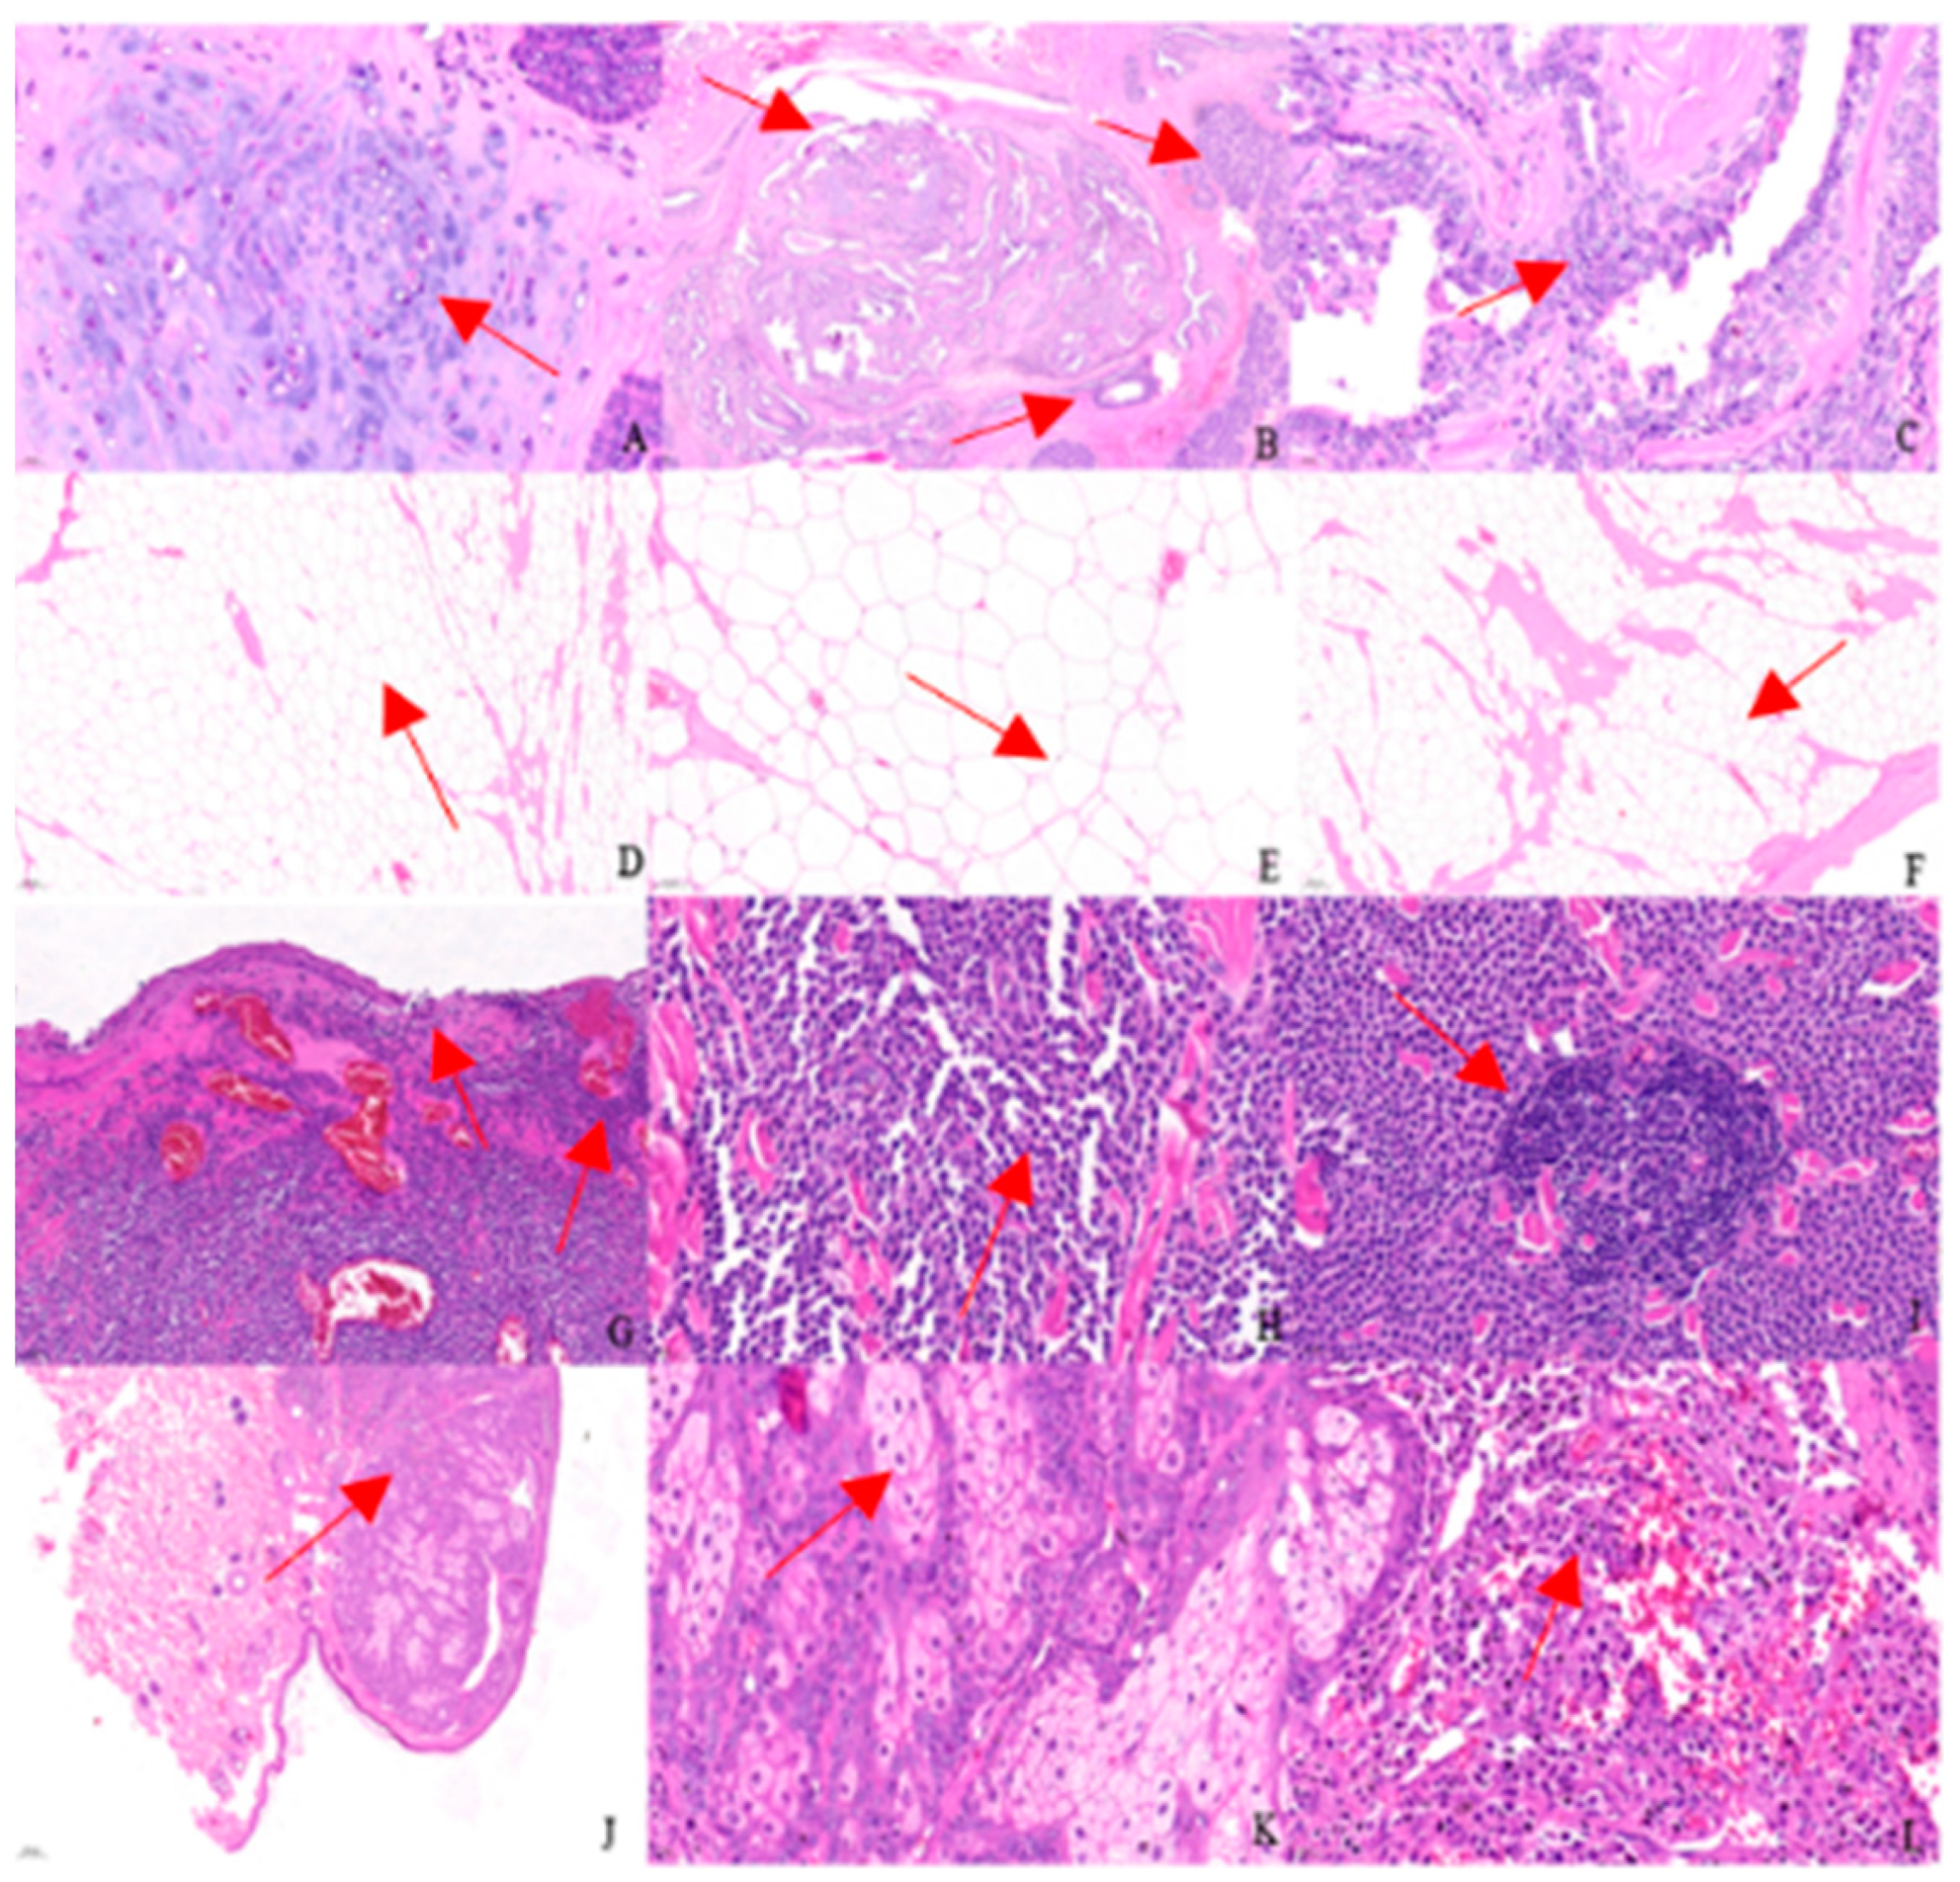

The results of pathological histological sections of canine tumours are presented in Figure 4. The red arrows in the picture indicate the abnormal location.

Figure 4.

(A–L) show the histopathological results in canine tumours.

Figure 4A–C show canine mammary tumours. Under high magnification, there is chondrogenesis within the mass (Figure 4A, arrow pointing), and a large number of hyperplastic glandular epithelium and myoepithelium are seen; the hyperplastic glandular epithelial cells are cuboidal to columnar, interconnected to form luminal or nested or lamellar forms (Figure 4B, arrow pointing), with a high nuclear-to-cytoplasmic ratio, occasional karyokinesis, and a moderate degree of anisotropy (Figure 4C, arrow pointing), and a high degree of anisotropy (Figure 4D–F, arrow pointing).

Figure 4D–F show canine lipomas. Under the microscope, the mass is seen to have an incomplete capsule, with a large number of proliferating adipocytes infiltrating into the transverse muscle fibres, which are separated into lobules by the muscle fibres and connective tissues, forming a marble-like appearance (Figure 4D,F, arrow pointing). The adipocytes are well differentiated, the cytoplasm is vacuolated, and the nuclei are extruded and distorted at the cell margins (Figure 4E, arrow pointing).

Figure 4G–I show a canine mast cell tumour. Under high magnification, the tumour cells and their nuclei in the ulcerated area are spindle-shaped (Figure 4G, arrow pointing); the interior of the mass is filled with hyperplastic cells, nearly round, with abundant cytoplasm and clear demarcation; the nuclei are round or oval, located in the centre, with one or two obvious nucleoli, and occasional binucleated cells are seen; cytokinesis is basically invisible, and the cells are well differentiated, with a low anisotropy and a “Holland egg-like” appearance (Figure 4H, arrow pointing). The cells are well differentiated with low heterogeneity, resembling a “ruffled egg-like” appearance (Figure 4H, arrow pointing). Local lymphocytic infiltration is seen within the tumour (Figure 4I, arrow pointing).

Figure 4J–L show a canine sebaceous adenoma. Under low magnification, the mass is seen as multiple basophilic mass-like structures located subcutaneously and well demarcated from the surrounding tissue (Figure 4J, arrow pointing). The interior of the lobules consists of proliferating sebocytes with abundant light-stained eosinophilic vacuolated cytoplasm and centrally located deeply stained small nuclei, with occasional mitosis (Figure 4K, arrow pointing). Infiltration of inflammatory cells is seen in close proximity of the mass to the skin (Figure 4L, arrow pointing).